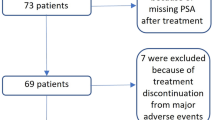

In this study, n = 66 patients with advanced mCRPC, who received [177Lu]Lu-PSMA-617 RLT in a palliative setting, were analyzed. Patients were treated at our institution within a prospective patient registry (REALITY Study, NCT04833517). Inclusion criteria for this study were confirmed mCRPC, at least 2 cycles of [177Lu]Lu-PSMA-617 RLT, [68Ga]Ga-PSMA-11 PET/CT before the first and after the second cycle of [177Lu]Lu-PSMA-617 RLT, absence of [18F]FDG/[68Ga]Ga-PSMA-11 mismatch findings (if additional [18F]FDG-PET/CT was performed), and availability of clinical outcome data. All patients received multiple therapies prior to PSMA-RLT, including ADT, NAAD, chemotherapy, and [223Ra]Ra-dichloride therapy. Detailed information about the patient characteristics is presented in Table 1. Between both PET scans, ADT and NAAD had to be continued unchanged to avoid altering PSMA expression [31]. PSMA-RLT was performed on a compassionate use basis under the German Pharmaceutical Act §13 (2b). Patients gave their consent after being thoroughly informed about the risks and potential adverse effects of PSMA-RLT. In addition, the patients agreed to the publication of the resulting data in accordance with the Declaration of Helsinki. The study was approved by the local Institutional Review Board (ethics committee permission number 140/17).